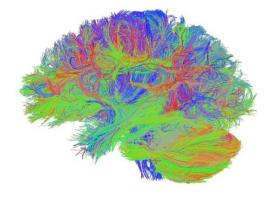

Actualité publiée il y a 8 années 9 moisCERVEAU : Il doit suivre aussi le bon régime alimentaire